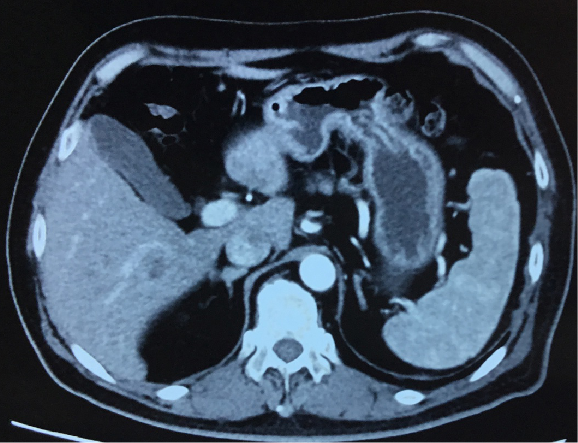

影像学检查:

CT提示:肝多发转移。

2016年12月CT:

2018年04月,CT提示肝转移

2018年11月CT提示肿瘤进展。

2019年01月复查CT提示病情无缓解。

2019年05月复查CT提示病情SD。